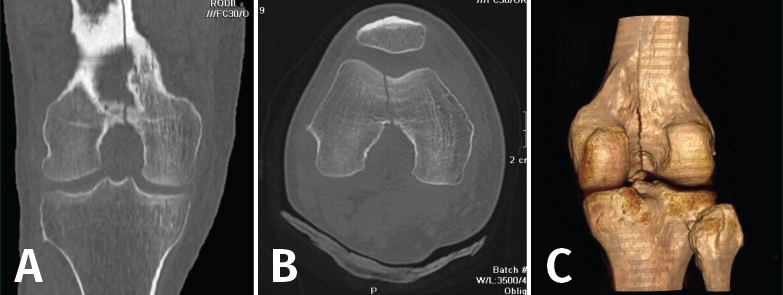

Figura 18. A: corte de reconstrucción coronal; B: axial; y C: reconstrucción 3D de tomografía axial computarizada de rodilla: fractura longitudinal del fémur extendida al techo intercondilar.

Es esencialmente útil en la valoración de los trazos de fractura, de su extensión, del escalón intraarticular y el desplazamiento. También es importante en la planificación del tratamiento de las fracturas intraarticulares complejas.

Los nuevos equipos, con múltiples detectores, permiten realizar cortes finos (submilimétricos) y reconstrucciones en cualquier plano del espacio o tridimensionales (3D) de gran calidad, que facilitan la valoración de estas lesiones(7).